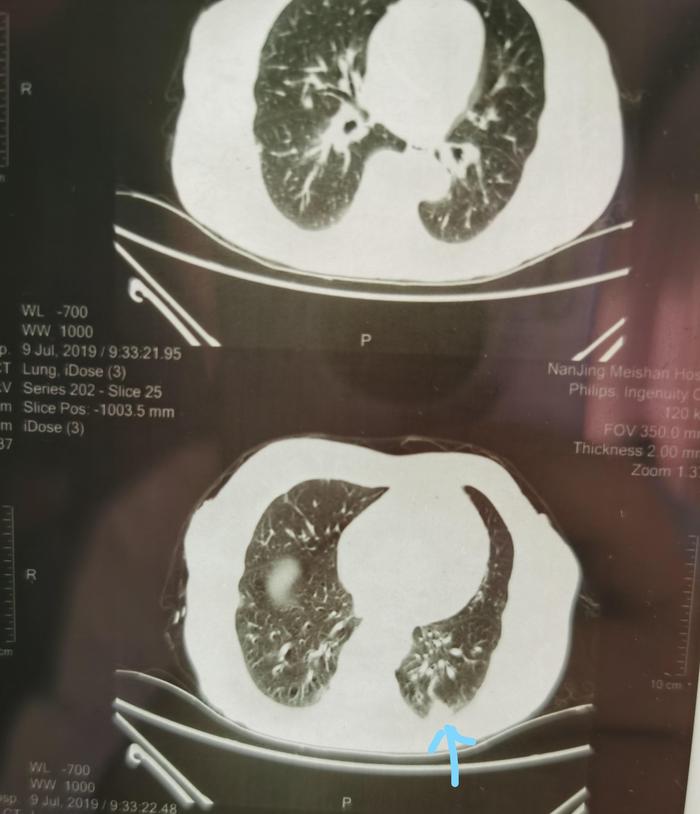

上图可见蓝色箭头指示的2019年7月左下肺混合磨玻璃结节,可见仍然为20毫米,变化不大。

上图为今年9月份住院后的CT,由两张CT组成。上面的CT的蓝色 箭头指向的是混合磨玻璃结节内部有一个腰果形缝隙,所以这个结节不是一个纯实性结节。下面的CT上面两个蓝色 箭头和左下方蓝色箭头指向的是结节内部小空泡(看起来在白色背景中发暗一些)。右边的蓝色箭头指向的是结节外侧有一小块磨玻璃成分。